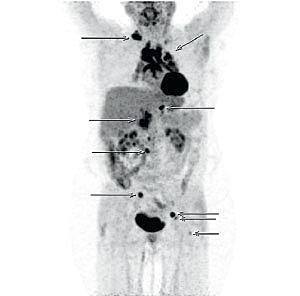

En 53-årig kvinde, der havde sarkoidose med involvering af øjnene og mediastinale lymfeknuder blev henvist til PET/CT til vurdering af sygdomsudbredelse inden terapistart. Der blev udført en PET/CT, som viste patologisk fluordeoxyglukoseoptagelse i multiple lymfeknuder fra hals til lyske, og derudover blev der fundet tre foci i knogler. På CT’en sås der varierende lymfeknudestørrelse, og der var ikke morfologiske forandringer i de positive knoglefoci, der var fundet ved PET.

Denne sygehistorie understøtter det potentiale, PET/CT har ved vurdering af sygdomsudbredelse hos patienter med sarkoidose.